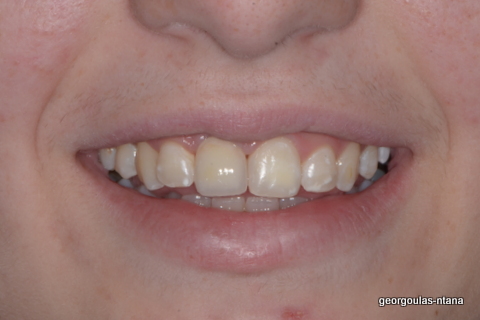

ΟΛΙΚΗ ΑΠΟΚΑΤΑΣΤΑΣΗ ΑΝΩ Κ ΚΑΤΩ ΓΝΑΘΟΥ ΜΕ ΕΜΦΥΤΕΥΜΑΤΑ, ΑΜΕΣΗ ΦΟΡΤΙΣΗ Κ ΑΝΟΙΚΤΗ ΑΝΥΨΩΣΗ ΙΓΜΟΡΕΙΟΥ